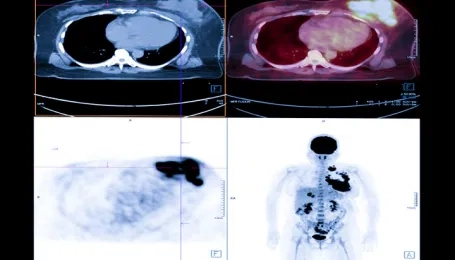

Nuclear Medicine methods are increasingly used in the treatment of cancer, as well as imaging. Targeted atomic therapies have been developing at a stunning pace since 2010.

Theragnostic is a field of medicine that combines patient-specific and disease-targeted diagnosis with treatment. The most important feature of atomic treatments with radionuclides is that the diagnosis can be made with the same drugs, and this provides an extraordinary advantage in cancer treatment. This feature ensures that the drug given for treatment, the area where it will reach in the body, and its effect on the diseased tissue are known precisely before the treatment. This approach is called the “theragnostic” approach.

Unlike conventional chemotherapeutics, theragnostic drugs go directly to the cancer cell, with little or no effect on normal cells. Thus, while healthy cells suffer the least damage, targeted therapy is performed by giving maximum damage to diseased cells such as cancer cells.